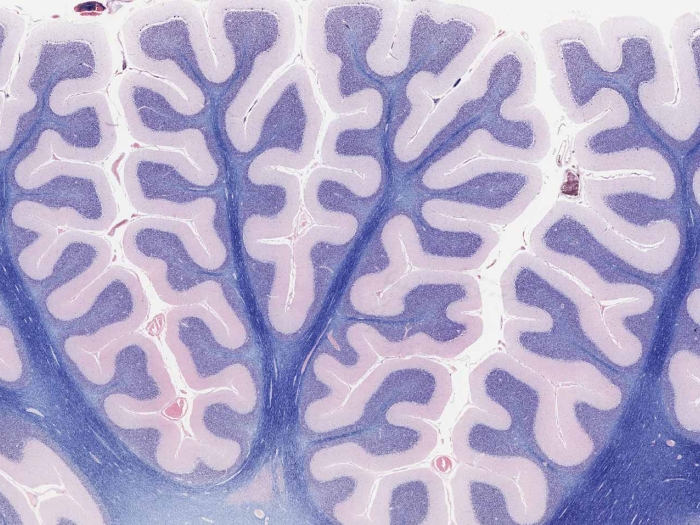

The Body’s Microscopic Environment, Free for Educators and Researchers Worldwide

When it comes to understanding the human body, seeing is believing. Now, a new website allows teachers and students anywhere to look through a “virtual microscope.”